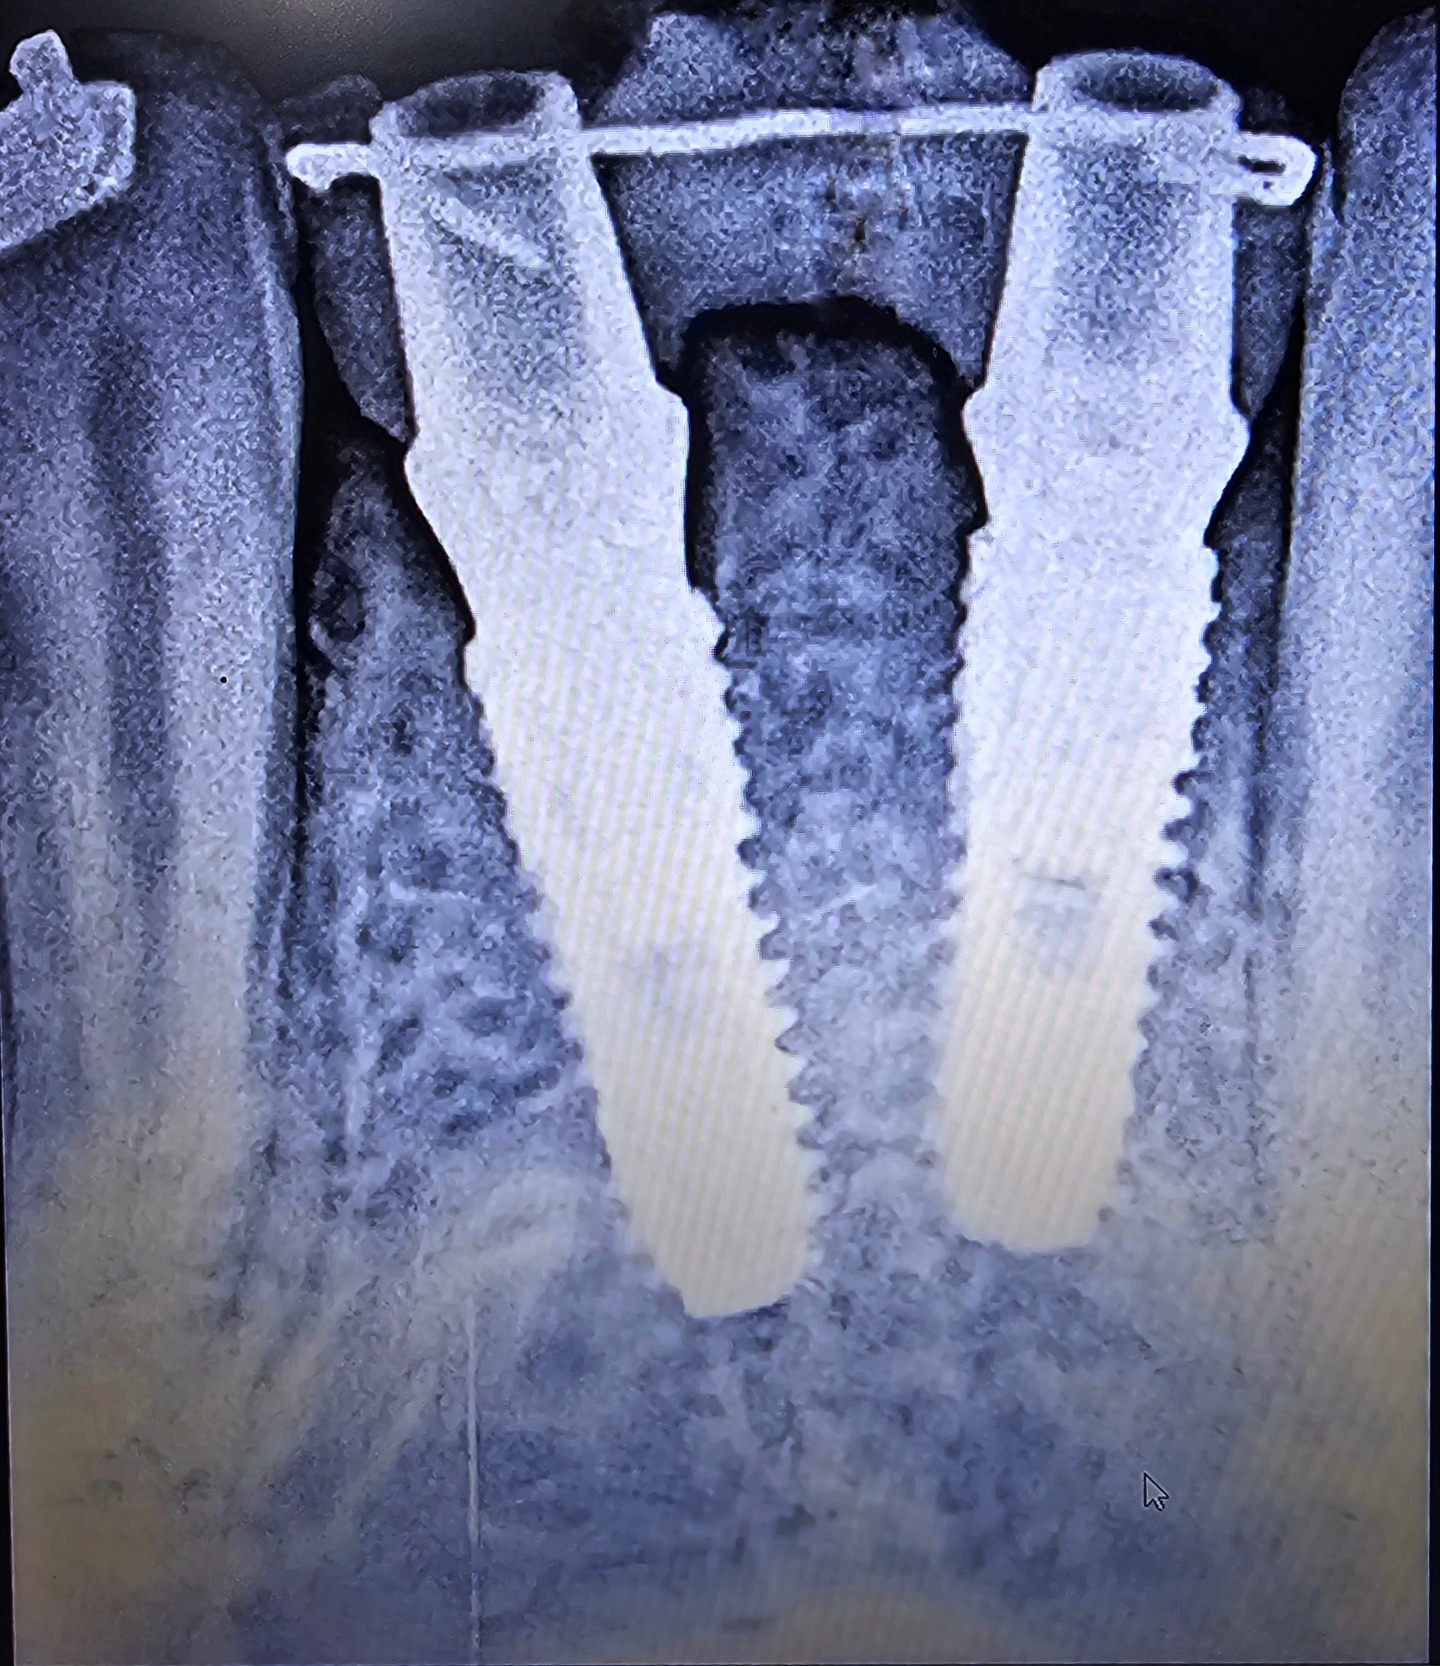

TREATMENTS OF THE ROOT CANAL

Our Dental Clinic offers top-quality root canal treatment that is designed to be a painless, comfortable experience for our patients. We use motorized instruments and LASER disinfection to ensure the best possible outcome. Additionally, we use high-grade materials for sealing to ensure that your teeth remain healthy and strong for years to come.

At our dental clinic, we understand the importance of maintaining healthy and strong teeth. Our Post and Core Build Up treatment is designed to do just that, by increasing the strength and durability of root canal treated teeth and preventing future fractures. Our team of experienced dentists use the latest techniques and materials to provide a reliable and long-lasting solution.